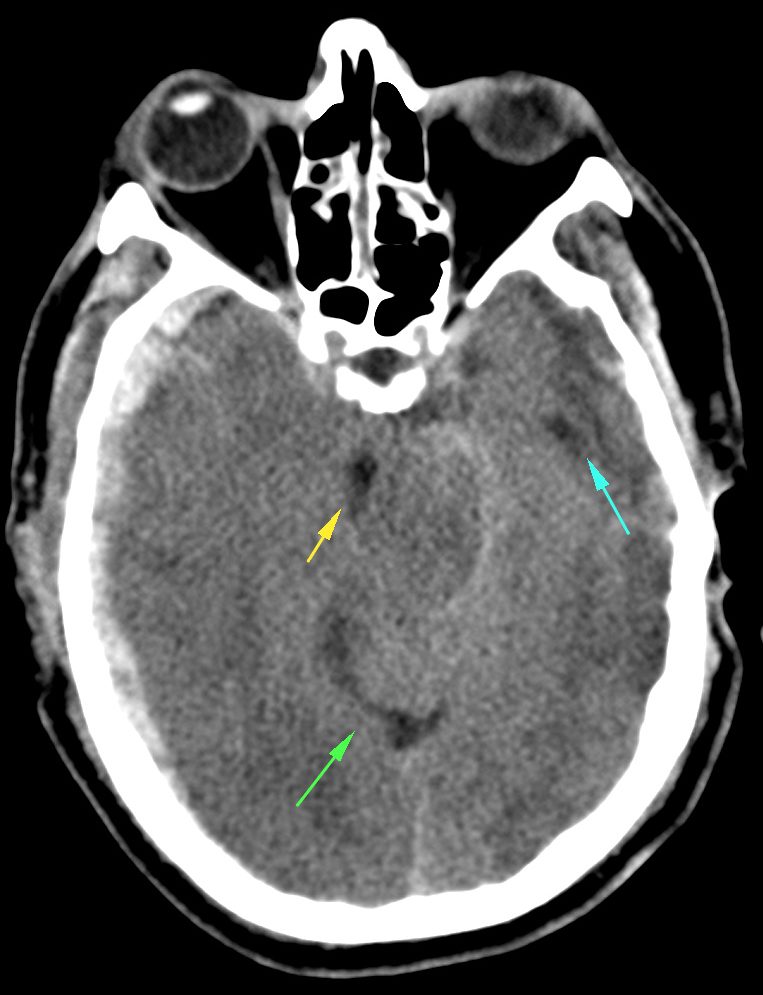

Transtentorial: puede ser unilateral/uncal o bilateral/central.

- Por descenso del contenido supratentorial a través de la tienda del cerebelo.

- Puede ser unilateral o Uncal = descenso del uncus hacia el interior de la cisterna supraselar.

- Dilatación del asta lateral contraletaral

- Dilatación de la cisterna ambiens y prepontina ipsilateral.

- Bilateral o Central = obliteración las cisternas basales

- Hay riesgo de infartos por compresión la ACP y perforantes.

- Pueden producir hemorragias de Duret (mesencéfalo) o de Kreonhan (pedúnculo cerebral contralateral)